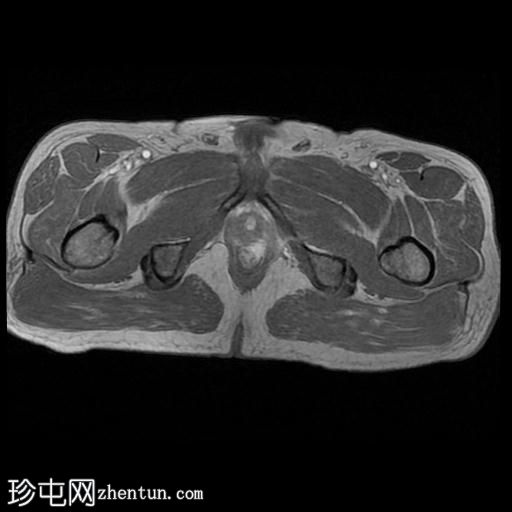

MRI

轴向位

T2

轴向位T2

脂肪饱和度

T1

轴向位T1

冠状位T1

冠状位

冠状位T2

C+脂肪饱和度

一条68毫米厚的强化通道始于左侧肛周区域,向上穿过肛门内外括约肌,在2点钟方向开口于肛管。

无脓肿形成。

MRI成像特征与所述左侧经括约肌肛周瘘相符。